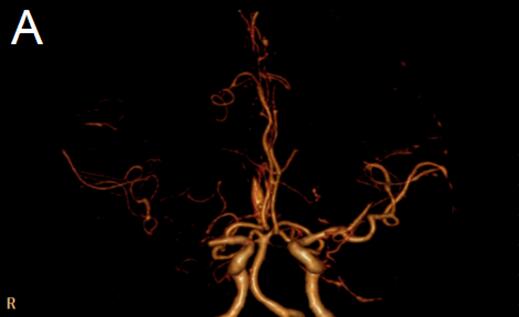

我院为患者立即开通卒中绿色通道,急查头颅DWI:右侧基底节、半卵圆中心、颞叶内侧、顶枕叶皮层多发急性梗塞灶,头部CTA显示右侧大脑中动脉M1段闭塞(图1);头部CT未见急性出血灶。诊断:“1.急性脑梗死;2.右侧大脑中动脉闭塞;3.高血压病2级 极高危组”明确。

图1 A:头颅CTA显示右侧大脑中动脉M1段闭塞(2017/9/6 18:38)